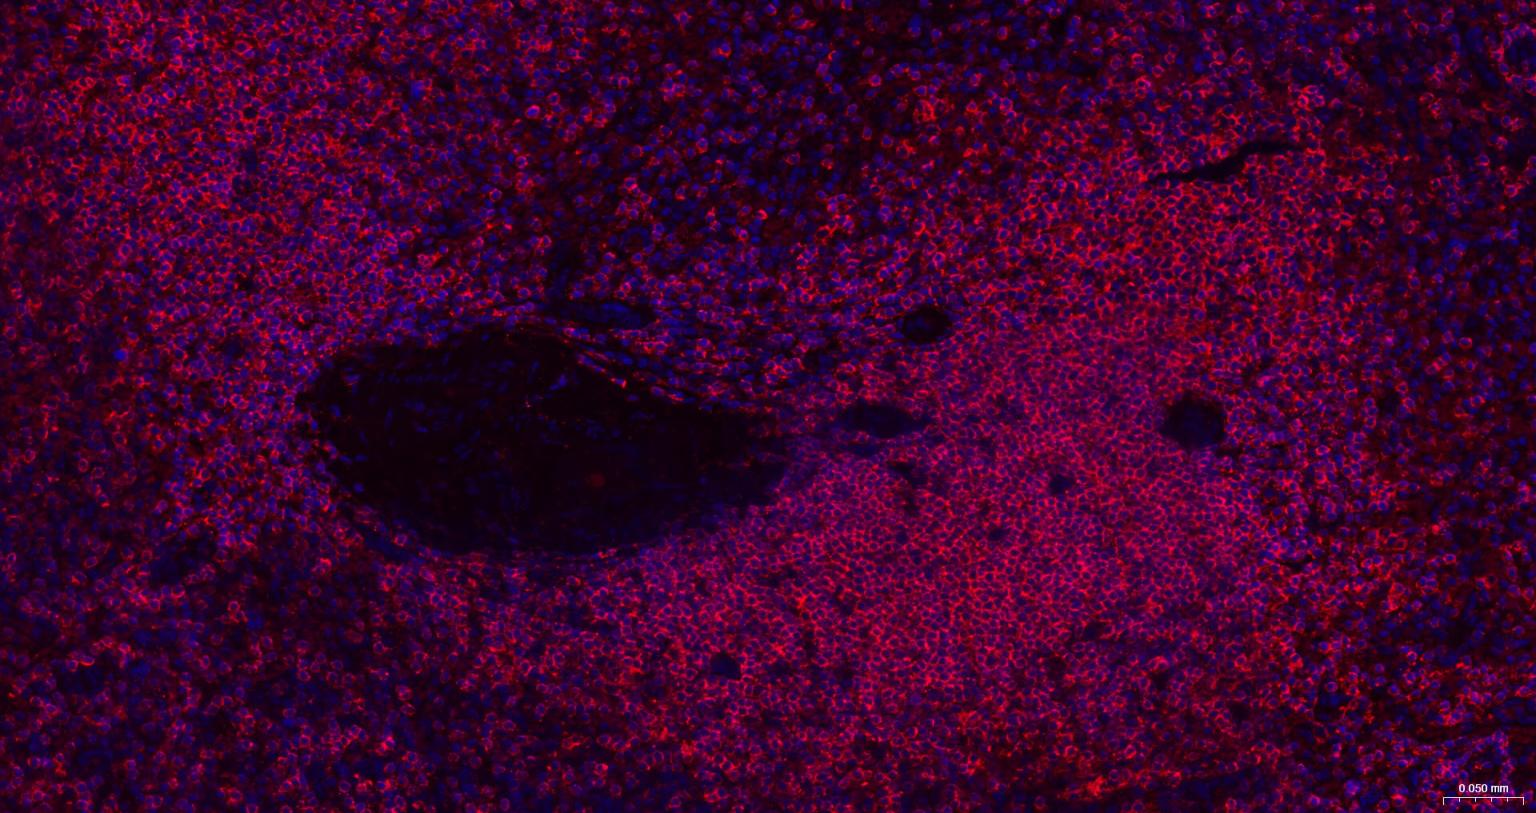

Paraformaldehyde-fixed, paraffin embedded Human Spleen; Antigen retrieval by boiling in sodium citrate buffer (pH6.0) for 15 min; The section was incubated with CD45 Monoclonal Antibody, Unconjugated (bsm-54757R) at 1:200 overnight at 4°C. Followed by conjugated Goat Anti-Rabbit IgG antibody (Red, bs-0295G-BF594), DAPI (blue, C02-04002) was used to stain the cell nuclei.